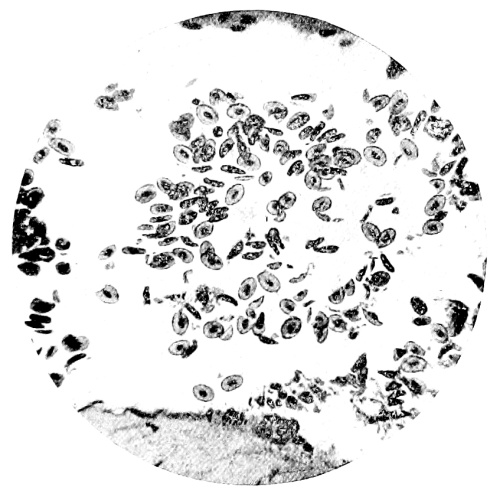

8. Measurement of Blood Corpuscles (human) 97

9. Measurement of Blood Corpuscles (sheep) 97

10. Photo-micrograph of Red Blood Corpuscles from Domestic Fowl 99

11. Photo-micrograph of Blood Corpuscles of Fish 99